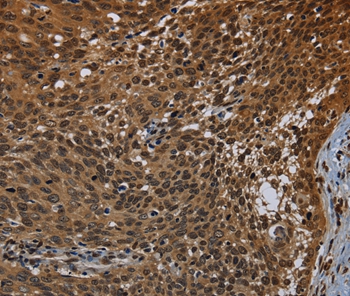

Immunohistochemical analysis of paraffin-embedded Human ovarian cancer tissue using #37805 at dilution 1/50.

Immunohistochemical analysis of paraffin-embedded Human cervical cancer tissue using #37805 at dilution 1/50.